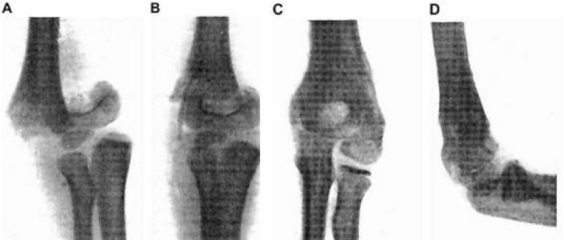

早在1907年,Lambotte就使用铁丝环扎术和一块带有六个钢螺丝的镁板来固定骨折的小腿,但是由于镁和铁接触后发生电化学反应,加速了镁的腐蚀,术后一天即观察到了大量的皮下气腔,并伴有局部有肿胀和疼痛。因此在排除了镁和其他金属混用后,Lambotte与其助手用镁钉治愈了4例儿童肱骨髁骨折,除发现气泡产生外,没有其它不良反应发生。 Jean Verbrugge在接下来的几年里,采用镁及其合金(AZ63和Mg-8wt.%Al)进行了25例骨折治疗的临床实验,如图2所示。由于镁在植入后的快速腐蚀降解,镁板和镁钉固定系统植入三周后,骨折线即消失不见。除此之外,有病人反映,植入部位会有暂时的麻木感觉,但没有组织感染迹象或不良反应发生。在这些病例中,因植入尺寸以及位置不同,镁在人体内在三个星期到一年最终吸收。 McBride进行的临床应用探索,发现镁可以加速治疗初期结缔组织的早期增殖和愈合组织的增生。1940年,Maier使用了由梭形镁片制成的针治疗肱骨骨折,并且在接下来的14年获得良好的恢复。 近年来,随着金属材料技术的发展,镁合金的力学性能和耐蚀性能均得到大幅改善。生物可降解金属新概念的提出,使镁基金属的医学应用研究又重新获得重视,针对可降解镁基金属材料在骨科植入物产品中的应用进行了大量的体内外研究。 在2005年,Witte等研究了铸态AZ31、AZ91、LAE442以及WE43四种工业用镁合金在豚鼠股骨内的植入行为。研究结果表明,在植入1周后所有实验组中均在皮下发现了H2气囊,但这些气囊在2-3周后自行消失,没有对豚鼠产生不良影响。同时,这四种镁合金表面在降解的过程中均形成了一层与周围骨组织直接接触的含Ca以及P的矿物层。与PLA对照组相比,在植入6周、18周之后,镁合金的植入显著的增加了骨膜处和骨内膜处新骨生成量。 2007年Duygulu等将AZ31镁合金螺钉植入羊的髋骨,在植入3个月后,螺钉发生了明显的降解,降解的部分被新生骨所取代。 近几年先后有纯镁及镁合金材料的临床植入研究报道。2013年,Windhagen等进行了MgYREZr合金空心螺钉进行脚拇指外翻手术后固定的临床研究工作。MgYREZr合金螺钉植入的6个月内,在植入部位没有观察到排异反应、骨溶解以及炎症反应,同时也未见跖趾关节强直现象。影像学检测表明,植入物部位没有发生缺血性坏死以及气体聚集。植入6个月后,MgYREZr合金螺钉未全部降解,骨组织已经完全愈合。 通过前期的基础研究和临床试验研究发现,可降解镁基金属具有良好的生物相容性和骨诱导性,同时由于材料科学的进步,其降解速率也能控制在合理的范围内,虽然由于其力学性能的不足,目前在临床上的应用范围具有一定的局限性,但其良好疗效已经预示着可降解镁作为骨科植入物具有广阔的发展前景。